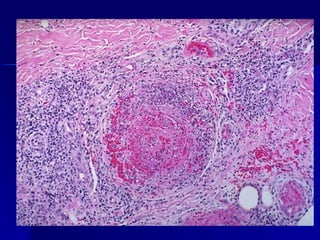

Inflamación crónica. Se observan linfocitos, células plasmáticas y algunos macrófagos

Inflamación crónica. Seobservan linfocitos, células plasmáticas y algunos macrófagos